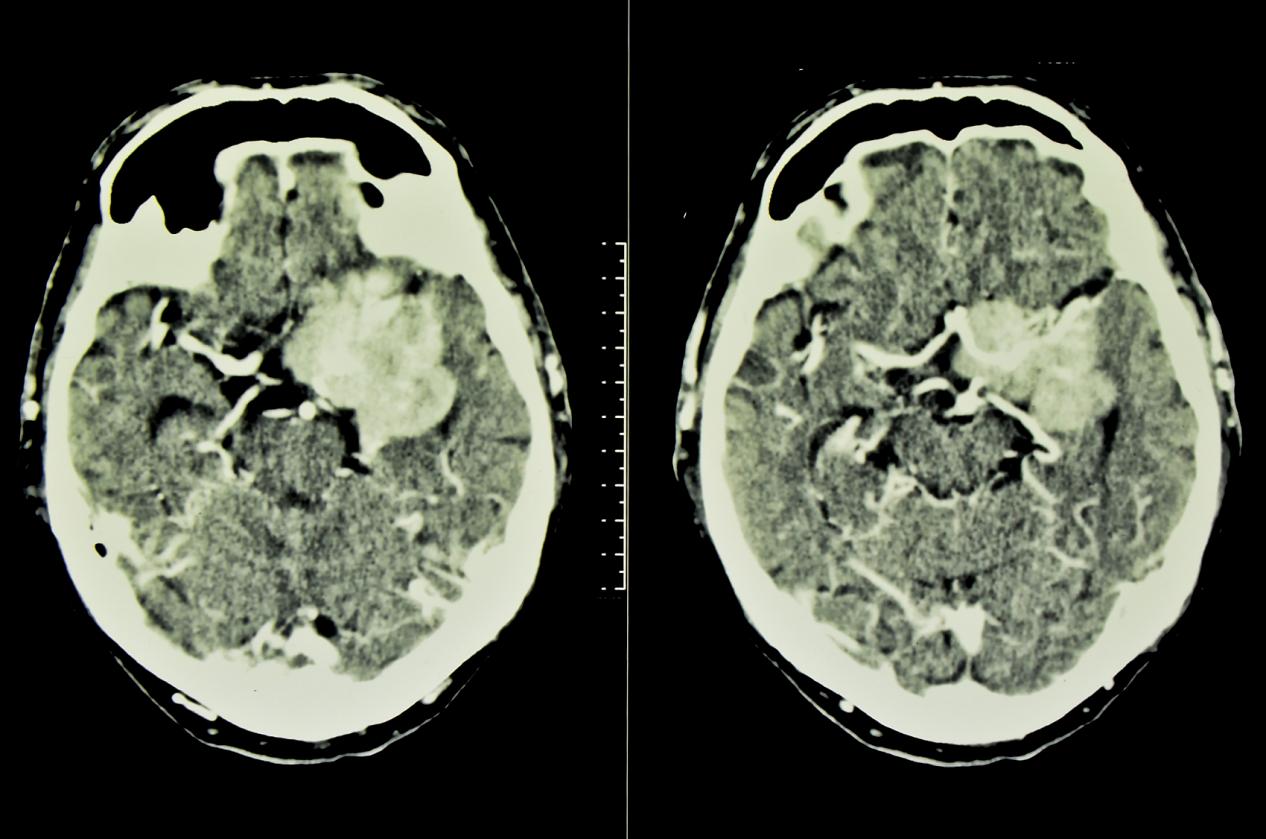

脑膜瘤的早期症状,昆明脑膜瘤医院推荐-昆明医科肿瘤医院脑膜瘤(Meningiomas)是起源于脑膜及脑膜间隙的衍生物,发病率占颅内肿瘤的19.2%,居第2位,女性:男性为2:1,发病高峰年龄在45岁,儿童少见。许多无症状脑膜瘤多为偶然发现。脑膜瘤是一种起源于脑...

脑膜瘤的临床表现,昆明脑膜瘤医院哪家好-昆明医科肿瘤医院脑膜瘤是一种常见的颅内肿瘤,它通常发生在脑膜(覆盖脑部和脊髓的薄膜)上。由于它的位置和生长速度不同,其症状和表现也会因个体差异而有所不同。但是,一些常见的症状和诊断方法可以帮助医生和患者及时发现和治疗脑膜...

昆明脑膜瘤放射治疗方式,昆明脑膜瘤医院哪家好-昆明医科肿瘤医院脑膜瘤(Meningiomas)是起源于脑膜及脑膜间隙的衍生物,发病率占颅内肿瘤的19.2%,居第2位,女性:男性为2:1,发病高峰年龄在45岁,儿童少见。许多无症状脑膜瘤多为偶然发现。脑膜瘤是指发...